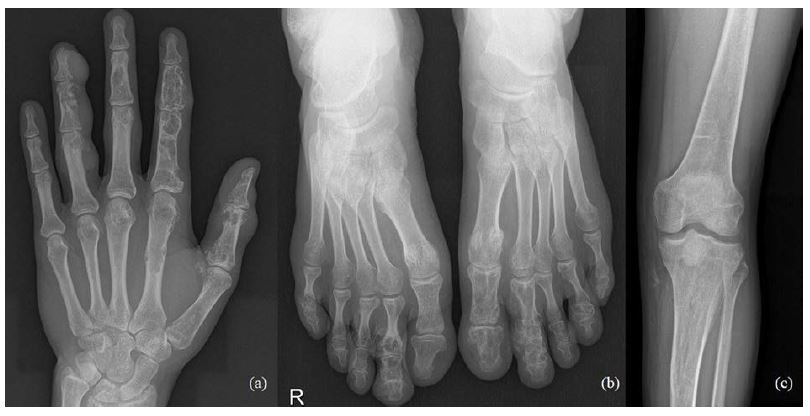

47-year-old man treated for 6 years in HLUHS for Ollier disease and chondrosarcoma. The patient underwent several surgeries in childhood due to leg deformities, different leg lengths – surgeries were performed with Ilizarov apparatus. In 2015 patient was referred to HLUHS outpatient clinic for long-term tiring pain in the left leg, difficulty walking – symptoms were intense and present for 5 years. Deformations were present in both legs. It was difficult to determine malignant changes due to severe anatomical changes. No radiographs were performed in 10 years. Arthritic changes were identified. Due to continuous pain, patient was consulted again after 8 months. Radiological examinations showed multiple zones of destruction, sclerosis in the distal part of the femur and an increase in bone density in the proximal part of the tibia. Progression of destructions was also seen. A biopsy was performed in January 2016, during which he was diagnosed with acute malignant chondrosarcoma G3. The production of a specialized oncological knee prosthesis, which was planned to be used during reconstruction after radical treatment, took 3 months. The patient was examined for the spread of the disease since chondrosarcoma metastases are most likely observed in the lungs [6]. During this time the disease progression was observed – lung metastases. In March 2016, tumor intraarticular resection and left knee replacement surgery were performed (Fig.1), partial resection of patella was performed due to observed changes, followed by adjuvant chemotherapy VIP (etoposide, ifosfamide, and cisplatin) according to the VIP protocol [7], and the treatment tactic was selected according to the ESMO Clinical Practice Guidelines for diagnosis, treatment, and follow-up [8]. In January 2017, relapse of the patella was observed. Patient refused amputation because metastases were diagnosed in the lungs. Due to observed changes patella resection was performed, followed by a reconstruction with donor patella and transplantation (Fig. 2). After surgery, VIP chemotherapy was continued till December 2017. In 2 years (2018–2019) 3 excisions of new malignant nodules in left tibia. The patient walked at bearing full weight, worked, knee flexion of 60 degrees was satisfactory for the patient. In 2020 amputation in the middle third of the thigh was performed because of possible pathological fracture, later 1 exarticulation through the hip joint was completed (Fig. 3). In total, patient had 7 surgeries. Currently it is 5 years of LWD (life with disease).